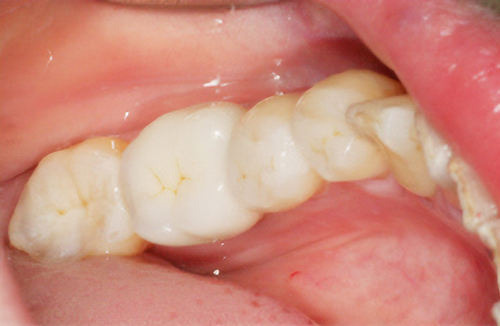

歯の形、歯並び、歯肉ラインが整う美しい口元

大掛かりな歯ぐきの手術や装置を使った矯正治療を行わずに、たった2回で歯並びをきれいに整えることができます。

術後

従来のセラミックで治すオールセラミックという被せ物や、セラミックを張り付けるラミネートべニアという方法に、歯科医師と歯科技工士の双方の手法と技法を癒合させることで、可能とした 歯ぐきのラインを2回の来院で、綺麗に仕上げ、歯の見た目も審美的に出来るテクニックのことである。

BTAテクニック® を用いると、歯ぐきや骨への手術が必要ない為に、治療期間が短縮でき、2回の来院で完了できるメリットがある。 また、この方法を用いることで、年々歯ぐきが下がって見た目が悪くなるということが起きにくくなる。歯周ポケットと言われる溝が浅くなり、歯ブラシが容易になる。などの利点が挙げられる特殊なテクニックである。